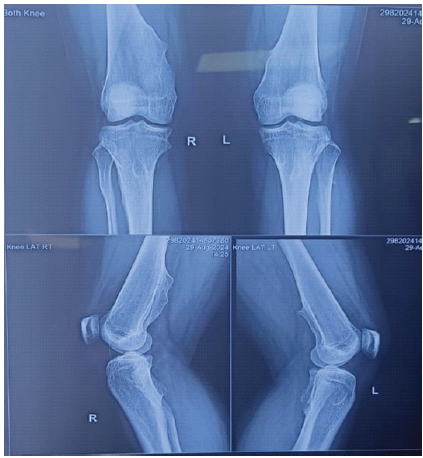

A 17-year-old female national-level football athlete presented with right knee pain, instability, and giving-way episodes following a twisting injury four months prior. She had a known history of HME with multiple bony swellings around her knees since childhood. Clinical examination revealed swelling, tenderness, and multiple palpable exostoses. Lachman, anterior drawer, and pivot shift tests were positive. Conservative management with bracing and physiotherapy failed. Radiographs showed multiple osteochondromas around the distal femur and proximal tibia (Fig. 1), and MRI confirmed a complete ACL tear without meniscal injury (Fig. 2).

Figure 1. Preoperative radiographs showing multiple exostoses around distal femur and proximal tibia.